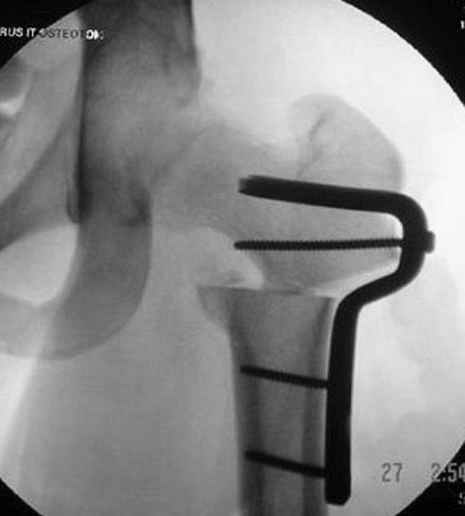

N3 рисунок окончательный снимок, после операции моя рентгенограмма должен выглядеть примерно как эта картина. На N4 снимке клин перед удалением; N5 послеоперации 3 нед.; N6 окончательная рентгенограмма.

варус при проксимальном отделе 95 градусной пластиной.